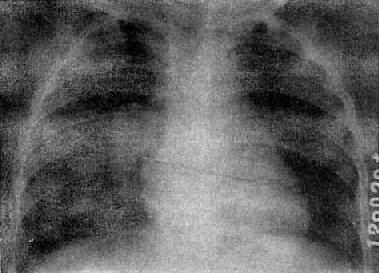

急性粟粒型肺结核

图3-1-22 急性粟粒型肺结核

两肺野布满粟粒状病灶,分布均匀,肺门大